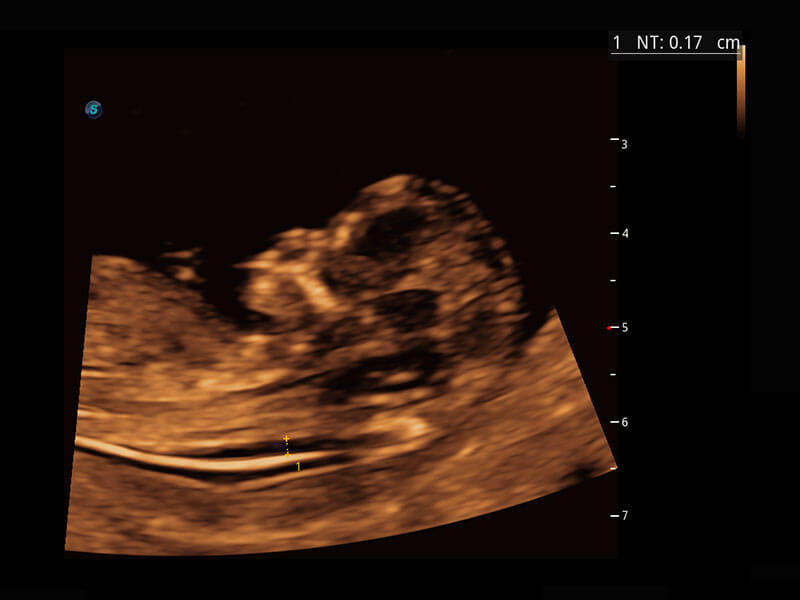

胎心筛查

P60搭载一系列胎儿心脏成像技术,实现精细的胎儿心脏评估。

• 四腔切面

• 四腔心血流